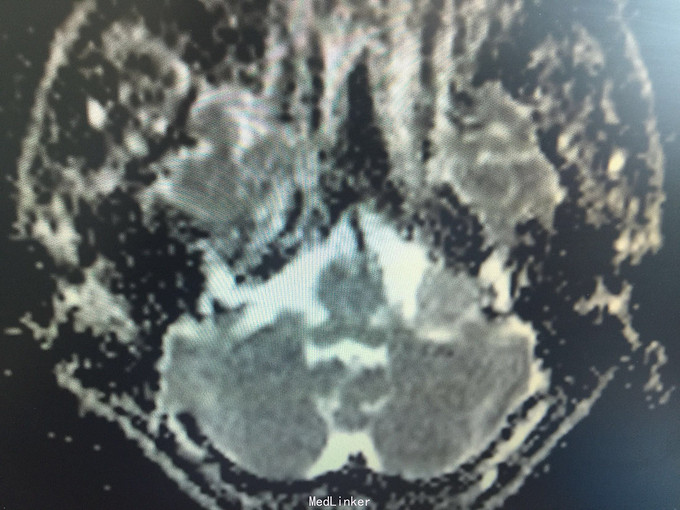

男,52岁,以“左耳鸣、听力下降1年余”入院。 现病史:1年余前看电视时出现左耳鸣、听力下降,左耳听电视声音时听不清,较右侧明显下降,未在意,之后听力下降逐渐至丧失! 既往史:既往高血压、糖尿病病史,长期吸烟病史。 家族史:无特殊!

查体:BP:150/90mmHg,心肺腹未见异常,神清语明,左耳听力丧失,无面瘫,双瞳孔等大正圆,直径约3.0mm,光敏,四肢肌力5级,肌张力正常,巴氏征R-L-。

1.左侧听神经瘤